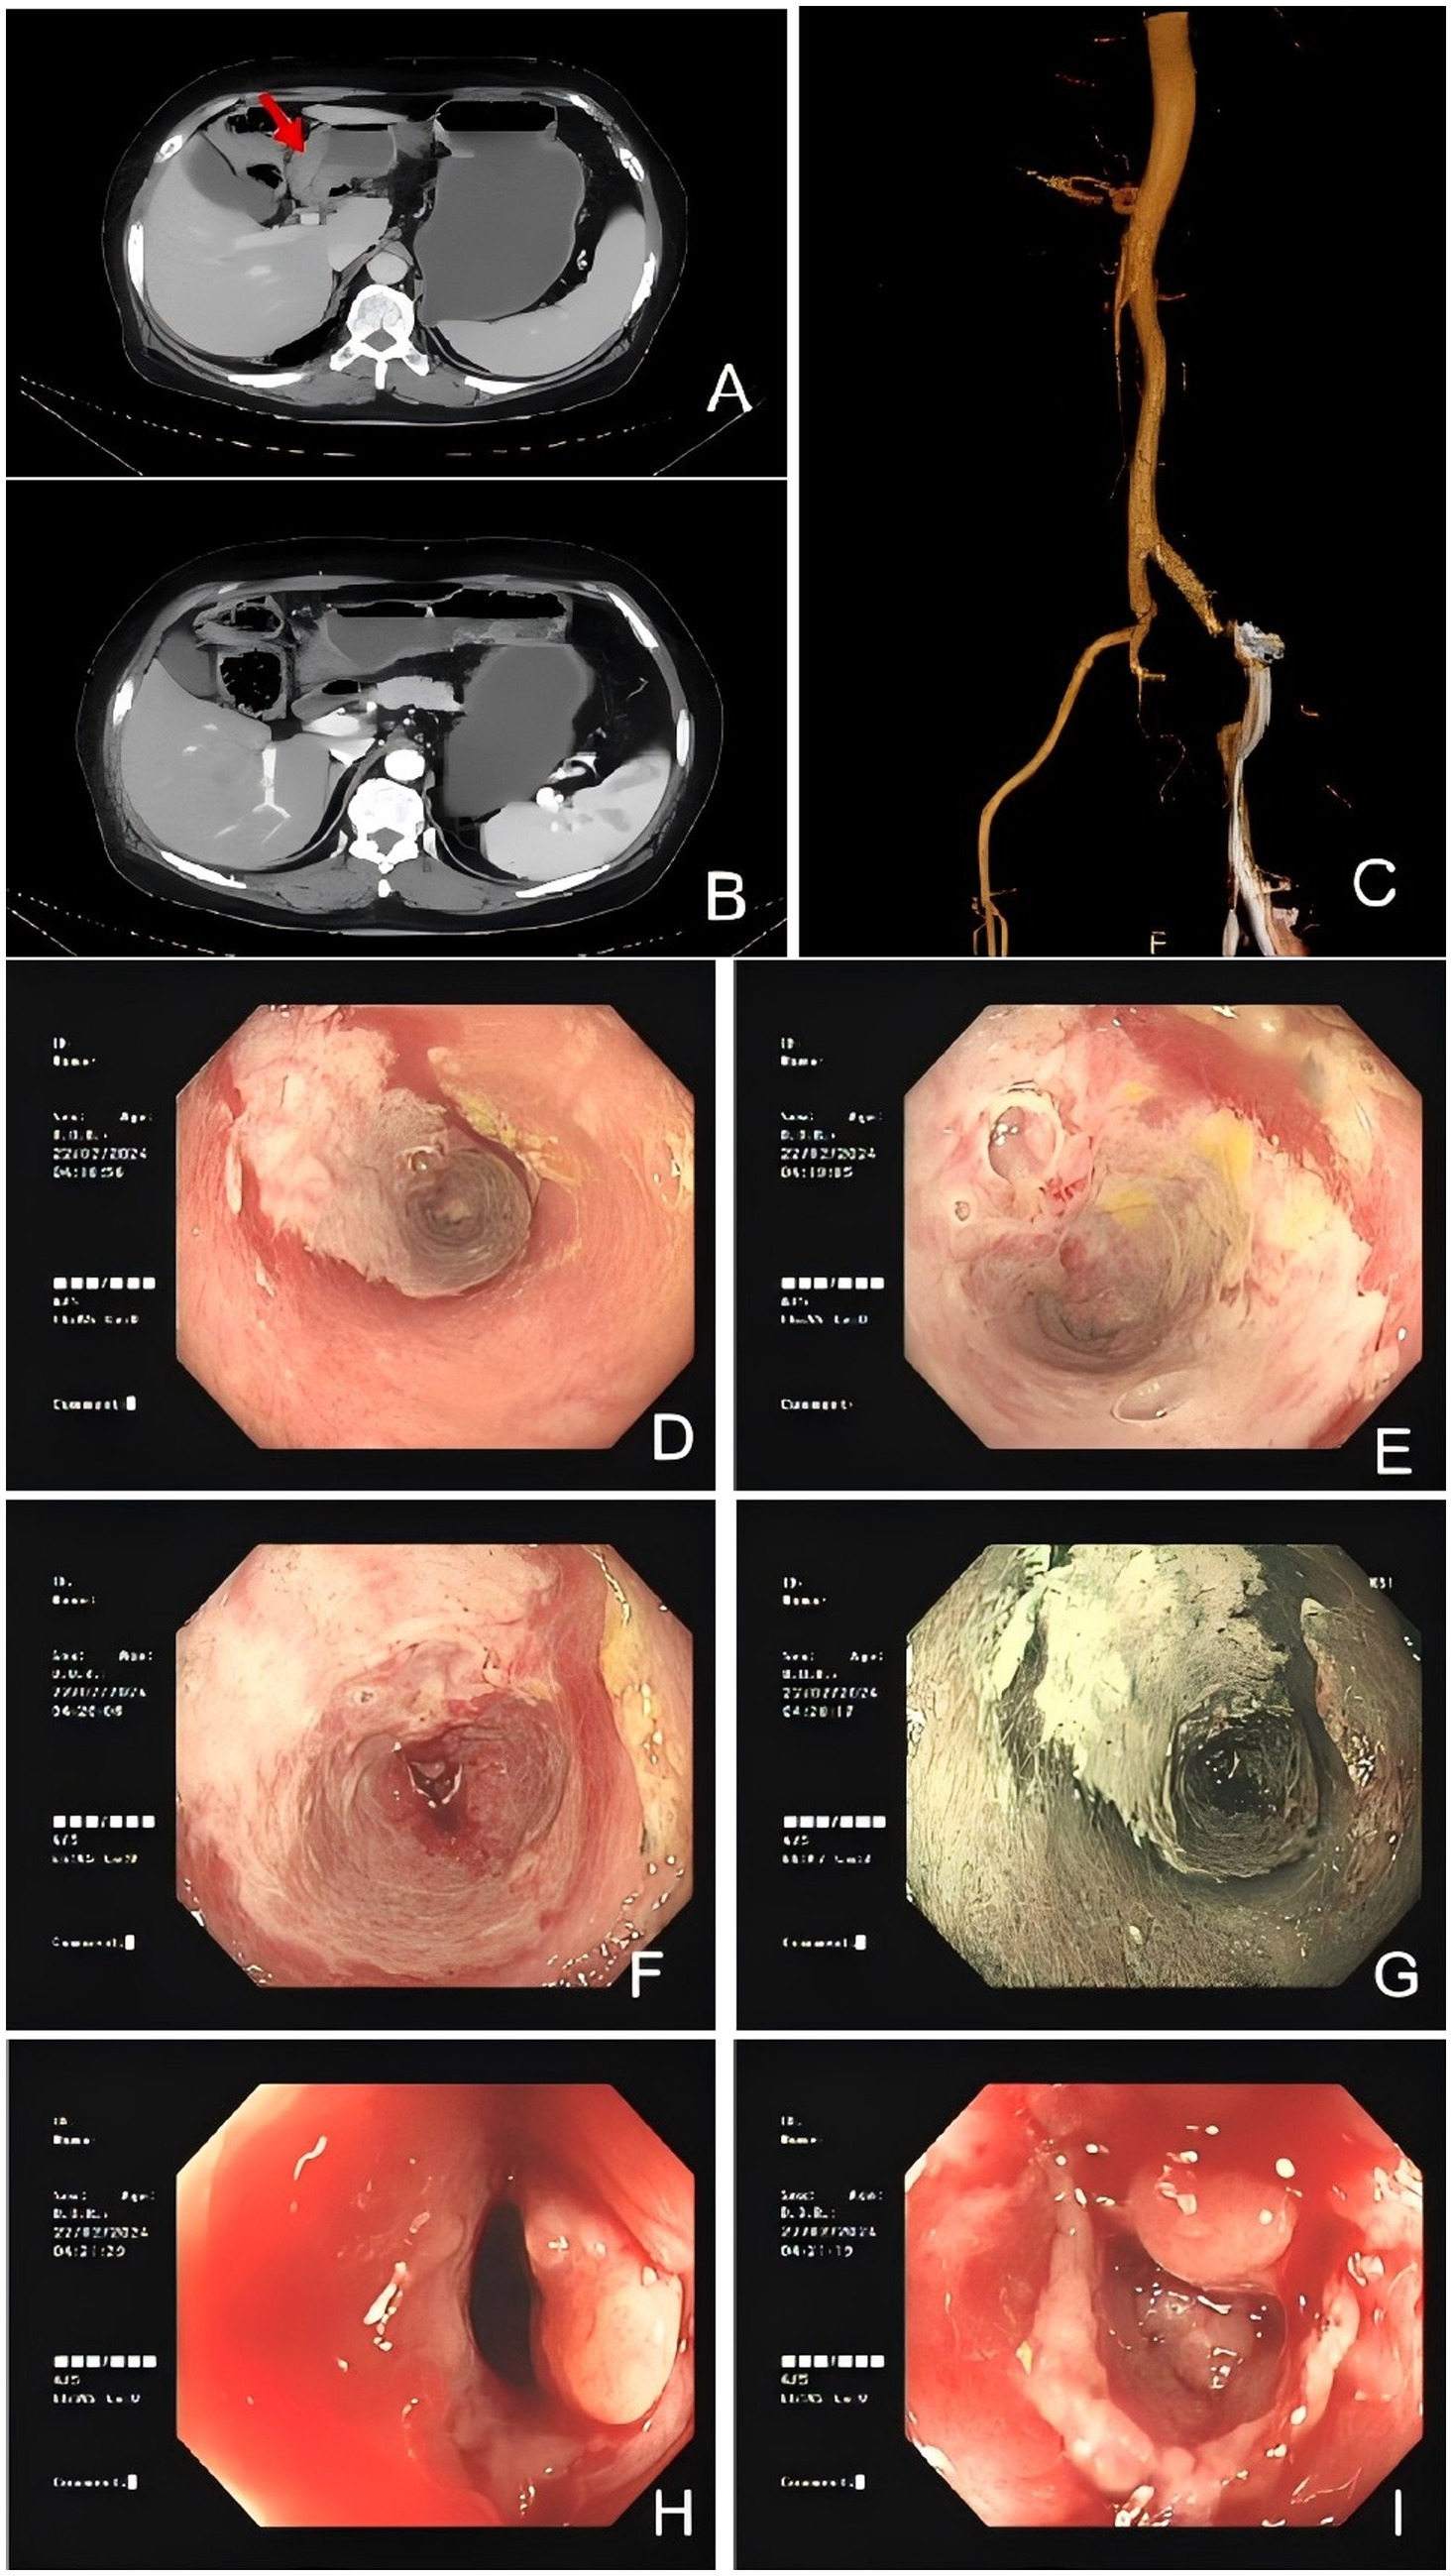

A colonoscopy revealed congested and inflamed mucosa in the colon (Figures 1DI). Salt and pepper appearance was seen in the region. The transverse colon exhibited a whitish appearance with loss of vasculature. Biopsy findings revealed a non-specific ulcer.

Figure 1. Colonic imaging and computed tomography suggested IMHMV. (A,B) Axial CT images showing thickened colonic wall with edema (red arrowhead) and no mesenteric artery stenosis. (C) Abdominal CTA revealed mixed plaques at the origin of the abdominal aorta and bilateral common iliac arteries, suggesting the possibility of mesenteric microthrombosis. Flexible sigmoidoscopy images demonstrated severely inflamed mucosa (D–J) with significant luminal narrowing (H,I).

Computed tomography angiography (CTA) of the abdomen showed mixed plaques in the abdominal aorta and at the origin of the bilateral common iliac arteries (Figure 1C). Computed tomography (CT) scan of the abdomen results showed a swollen colon wall with diminished enhancement and surrounding exudate that was suggestive of ischemic bowel disease (Figures 1A,B). Based on the presentation and investigative findings, she was diagnosed with a suspected case of ischemic bowel disease and was started on scopolamine hydrobromide for spasm and pain relief, fasting, omeprazole for gastric protection, and atorvastatin calcium tablets to stabilize plaques. The patient’s abdominal pain slightly subsided, but intermittent abdominal pain persisted, primarily around the navel, with slight relief after activity or oxygen inhalation. The stools were yellow and pasty. Papaverine was additionally used to relieve spasm and improve intestinal blood supply, while mesalazine was administered to repair the intestinal mucosa. Metronidazole tablets were added to treat the infection, but the patient experienced nausea and acid reflux after administration. Additionally, no pseudomembranous enteritis was found in the colonoscopy, and there was no mucus or pseudomembranes in the stool. Metronidazole was discontinued after 1 week. A conservative management approach was followed, but the symptoms did not resolve. A decision was made to proceed with a laparoscopic right hemicolectomy.

The most common symptoms reported in previous cases include abdominal pain, perforation, and hematochezia (Supplementary Table S1). The patient was admitted with chief complaint of severe abdominal pain. Patients with C. difficile enteritis generally present with diarrhea, crampy abdominal pain, and leukocytosis (6). Given that the patient presented with Clostridium difficile infection (CDI) and the clinical manifestations of IMHMV and pseudomembranous colitis caused by CDI were similar, the histological findings were distinctly different. The former often results in mucosal changes due to non-specific ischemic injury, rather than a toxin-mediated inflammatory process, with the absence of pseudomembrane formation and interstitial necrosis (7). CDI may lead to microvascular dysfunction and thrombosis of the superior mesenteric artery (8, 9) and affect the development of ischemic bowel disease (10). Ischemic colitis may be a complication of CDI (11). As a rare cause of ischemic bowel disease, CDI may offer insight into the pathogenesis of IMHMV. This case is notable as the first reported instance of IMHMV combined with CDI. CT imaging of our patient revealed focal colonic wall thickening and submucosal edema with preserved mesenteric arterial patency. However, the characteristic radiographic findings of IMHMV described in previous reports—enlarged and tortuous pericolonic vessels with rich, dilated peripheral veins—were not observed in this case (Figure 1). This absence may reflect the early stage and limited extent of venous involvement in our patient, as well as differences in imaging protocol compared with prior studies (Table 1).